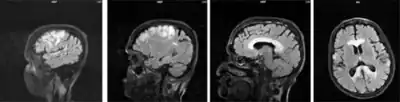

Marchiafava–Bignami disease is routinely diagnosed with the use of an MRI because the majority of clinical symptoms are non-specific. Before the use of such imaging equipment, it was unable to be diagnosed until autopsy. The patient usually has a history of alcohol use disorder or malnutrition and neurological symptoms are sometimes present and can help lead to a diagnosis. MBD can be told apart from other neural diseases due to the symmetry of the lesions in the corpus callosum as well as the fact that these lesions don't affect the upper and lower edges.[4]